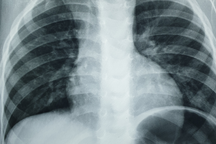

Hình ảnh dị vật trên phim chụp X-quang.

Qua thăm khám, các bác sĩ chẩn đoán đây là một trường hợp dị vật đường tiêu hóa. Ngay sau đó, các bác sĩ đã tiến hành gây mê nội khí quản và nội soi dạ dày. Dị vật gắp ra một sợi dây chuyền dài khoảng 40cm. Sau nội soi, trẻ tỉnh và đã có thể ăn uống trở lại.